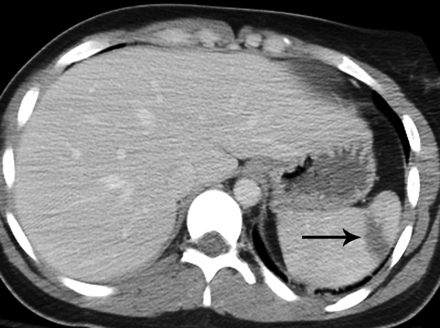

Low grade lacerations are associated with bleeding in and around the spleen but do not involve the major blood vessels surrounding the spleen. The decision to observe versus operate has long been controversial for splenic injuries, but most low-grade lacerations are observed closely with blood tests and imaging studies to ensure that the bleeding resolves on its own.

The concern with a low-grade laceration is delayed rupture, which can occur if the laceration continues to enlarge through the capsule of the organ due to inflammation around the capsule tissue or continued slow expansion of a hematoma under the capsule itself. It’s difficult to say exactly what the risk of delayed rupture, but most studies suggest the risk extends to 7-14 days after the initial injury and show that most delayed ruptures occur with the first ten days. That likely explains the reports that Witten isn’t expected to have surgery, but that it hasn’t been ruled out.